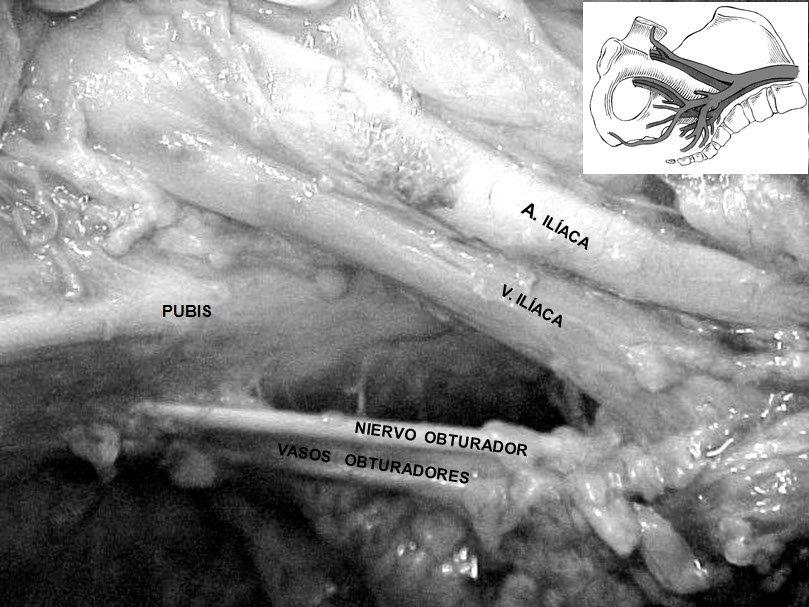

Anastomosis entre vasos ilíacos y obturadores en la región retropúbica: estudio en cadáveres. [Anastomosis among iliac vessels and obturators in the retropubic region: Study in cadavers].

IntroducciónEn las cirugías de la región retropúbica, la sección o ruptura de la anastomosis puede causar graves hemorragias de difícil control. Nuestro objetivo fue verificar la presencia o no de anastomosis arterial o venosa entre los vasos ilíacos y obturadores en la región retropúbica.Materiales y MétodosTreinta cadáveres (14 hombres/16 mujeres; 60% de raza blanca y 40%, no blanca). Después de la disección, se verificó si había anastomosis y su distancia de la sínfisis púbica.ResultadosEl 13,3% no tenía comunicación y el 86,6% tenía algún tipo de anastomosis (p <0,01), la anastomosis venosa fue la más frecuente (p <0,05). La distancia promedio entre la anastomosis y la sínfisis púbica fue de 5,7 cm. Al comparar el sexo, la anastomosis y el lado, el 57% de los hombres presentaba anastomosis en ambos lados, y el 81% y 88% de las mujeres la tenían en el lado derecho e izquierdo, respectivamente (p <0,05). Cuando se comparó la presencia de anastomosis con el lado, el 70% estaba en el derecho y el 73%, en el izquierdo (p >0,05). El 72% de los blancos y el 67% de raza no blanca tenían anastomosis (p >0,05).ConclusionesLa presencia de anastomosis es más frecuente que la ausencia y no existe diferencia significativa en cuanto al lado. Está localizada, en promedio, a 5,7 cm de la sínfisis púbica y la venosa es significativamente más frecuente. Es significativamente más frecuente en las mujeres. No hay diferencia estadística en cuanto a la presencia de anastomosis entre la raza blanca y no blanca.Descargas